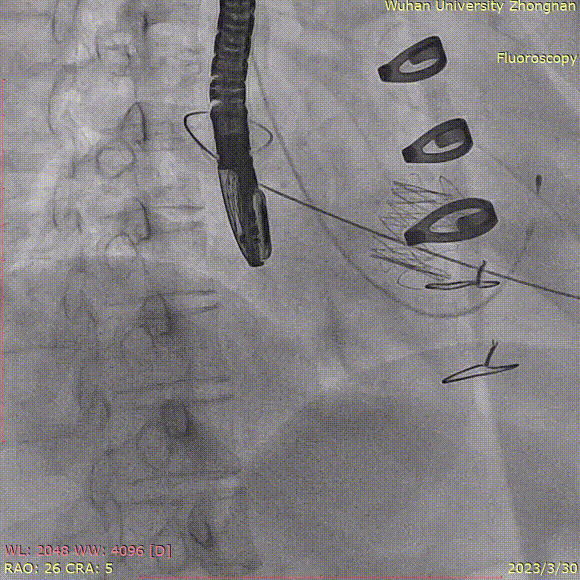

定位件于瓣环下打开,将瓣膜件降至合适平面,造影确认:

定位件入窦,造影:

调整导丝,使得瓣膜同轴:

再次造影确定位置:

释放瓣膜,复查根部造影,未见明显反流,瓣膜形态和位置满意,双侧冠脉未见遮挡征象: